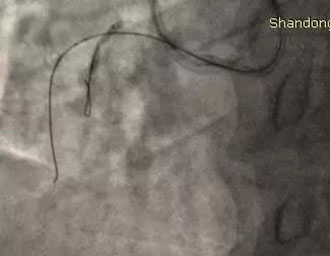

图二:导丝自近端进入内膜下,钝性分离内膜下组织